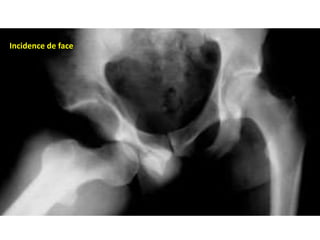

• Imagerie:

La Radiographie conventionnelle: La réalisation d’un bassin de face

est le minimum nécessaire et obligatoire chez un polytraumatisé,

surtout si celui-ci présente des troubles de la conscience.

Des clichés de profil ou de trois quarts sont réalisés au moindre

doute.

Il faut analyser la symétrie des interlignes coxofémoraux, le respect

du cintre cervico-obturateur, la position des hanches en rotation et

la taille respective des têtes fémorales (effet d’agrandissement). Il

faut également rechercher une lésion osseuse associée du bassin

ou de l’extrémité supérieure du fémur.

• En l’absence de lésion associée, aucune autre iconographie n’est

indispensable avant réduction car il permet de poser le

diagnostique de la luxation et de préciser sa variété.

Incidence de face